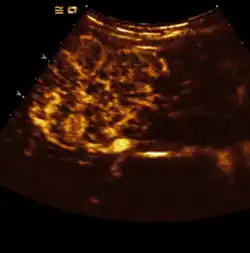

- Detektion und Charakterisierung von Lebertumoren: Das Muster und der Zeitpunkt der Kontrastmittelaufnahme von Veränderungen in der Leber macht in vielen Fällen eine genaue Artzuordnung möglich. Hier macht man sich eine Besonderheit der Leber zunutze. Im Gegensatz zu den meisten anderen Organen (Ausnahme Hypophyse) besitzt die Leber eine duale Blutversorgung: neben der Leberarterie wird das Organ über die Pfortader versorgt, welche nährstoffreiches Blut aus dem Darm zuführt. Spritzt man Kontrastmittel in eine Armvene, so wird dieses zuerst über die Arterien in die Leber gelangen (um dort u. a. die Gallenwege mit Sauerstoff zu versorgen), anschließend stellt sich das Kontrastmittel abfließend in den Lebervenen dar. Die Anflutung des Kontrastmittels in der Pfortader dauert am längsten (30–40 s), da das Blut erst im Darm zirkuliert und anschließend zur Leber gelangt. Lebereigenes Gewebe wird also auch in dieser sog. Spätphase Kontrastmittel enthalten. Metastasen leberfremder Tumoren enthalten natürlich kein Pfortadersystem und erscheinen daher kontrastmittelfrei (dunkel).

Manche Tumoren stellen sich im Kontrastmittelverstärkten Ultraschall so typisch dar, dass bei ihnen auf eine Leberbiopsie mittlerweile verzichtet wird.- Fokale noduläre Hyperplasie (FNH): Wird von einem Gefäßsystem mit Radspeichenmuster versorgt.

- Hämangiom: Aus dem zeitlichen Verlauf des Kontrastmittelanflutung von außen nach innen („Irisblenden-Phänomen“) wird auf ein Hämangiom geschlossen.